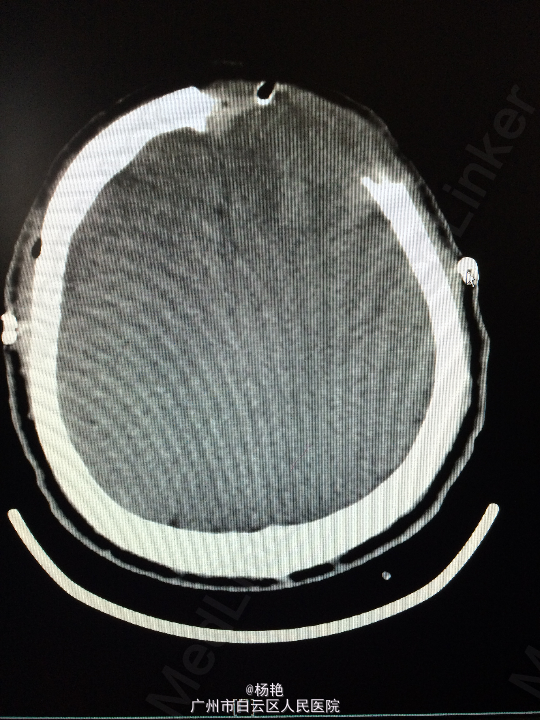

主诉:反复头痛2年加重1周 病史:患者诉两年前无明显诱因反复出现头晕头痛不适,近一周来症状加重,无恶心呕吐、无行走不稳、肢体乏力、意识障碍等。遂至当地医院诊治,行头颅CT、MR检查均提示颅内占位,良性可能性大,考虑脑膜瘤。今患者为求进一步治疗而入我院。

查体:神经系统查体未见明显异常 辅助检查:头颅MR提示:左侧额叶区域较大类圆形肿物,多考虑脑膜瘤可能;大脑前动脉及中动脉受压,中线偏移。

诊断:左额叶脑膜瘤 处理:在静脉全麻下行左侧额底脑膜瘤切除术,术后病理提示:脑膜瘤